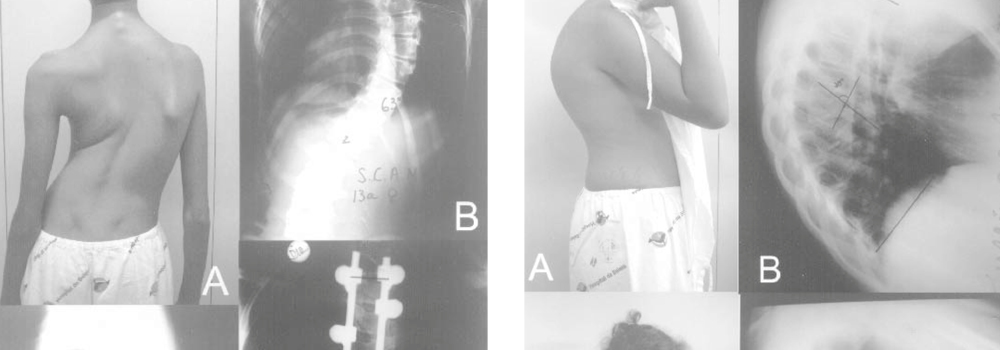

Sistema de parafusos pediculares no tratamento de deformidades vertebrais: análise da correção e das complicações imediatas

DR RODRIGO D’ALESSANDRO Objetivo: O objetivo deste estudo é determinar o grau de correção das deformidades, as complicações imediatas e as características da amostra. Métodos: Foram estudados prospectivamente 43 pacientes submetidos à instrumentação com o uso do sistema de parafusos pediculares para tratamento de deformidades, de maio de 2002 a janeiro de 2004. Foram utilizados […]